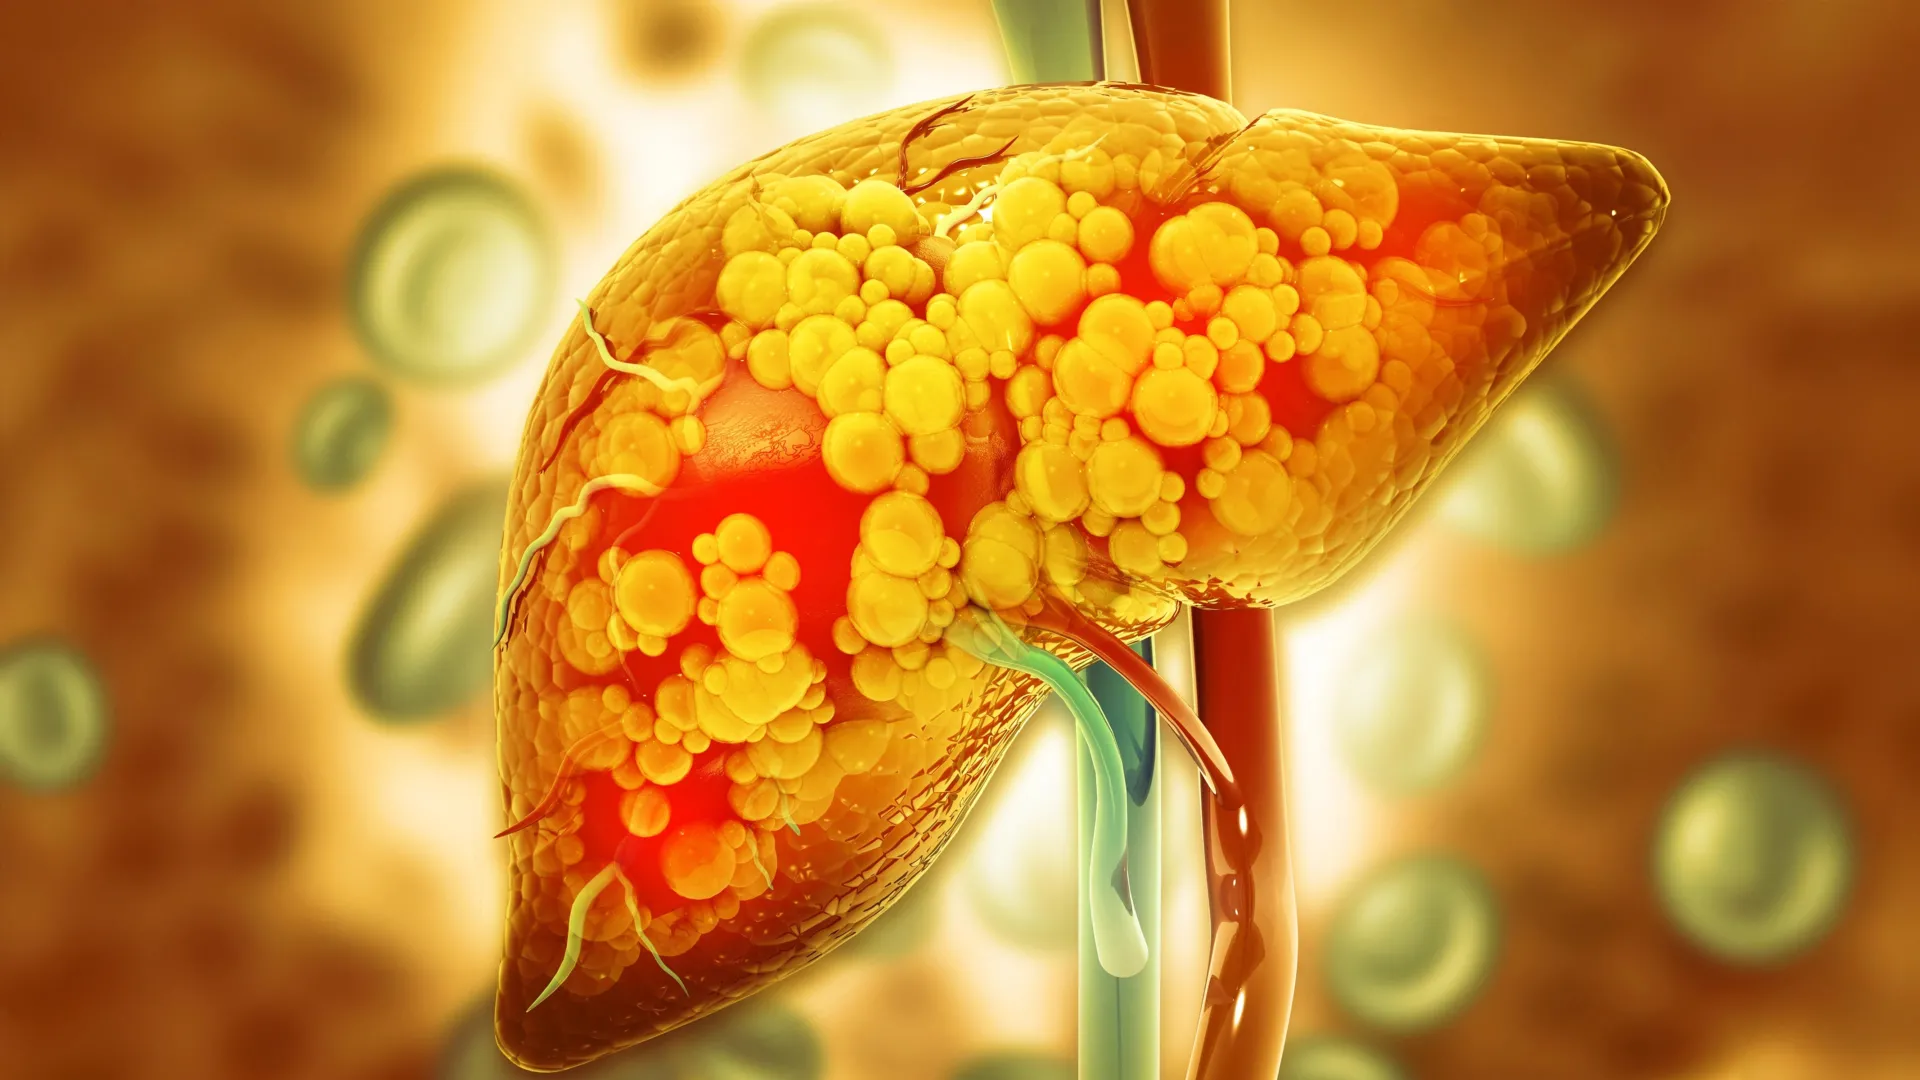

Children whose mothers eat a diet high in fat and sugar during pregnancy and breastfeeding face a greater chance of developing fatty liver disease later in life. New findings from the University of Oklahoma suggest that this risk may be lowered. In the study, pregnant and nursing mice given a naturally occurring compound made by healthy gut bacteria had offspring with much lower rates of fatty liver disease as they grew older.

The compound studied is called indole. It is produced by beneficial gut bacteria when they break down tryptophan, an amino acid found in foods like turkey and nuts. The results add to growing research focused on preventing metabolic dysfunction-associated steatotic liver disease (MASLD). This form of fatty liver disease affects both adults and children, but it often advances more quickly in children and is closely linked to diabetes.

“The prevalence of MASLD in children is about 30% in those with obesity and about 10% in children without obesity,” said Jed Friedman, Ph.D., director of the OU Health Harold Hamm Diabetes Center and professor of biochemistry and physiology in the OU College of Medicine. “Unfortunately, the risk is higher if a mother is obese or consumes a poor diet. The disease in children is silent and typically isn’t discovered until a parent seeks help for their child for liver-related symptoms.”

Offspring born to mothers that received indole showed multiple health advantages. They had healthier livers, gained less weight, maintained lower blood sugar levels, and developed smaller fat cells, even after being exposed to an unhealthy diet later in life. The researchers also observed activation of a protective gut pathway involving the acyl hydrocarbon receptor (AHR).

The study found no increase in harmful liver fats known as long-chain ceramides, while levels of beneficial very long-chain ceramides rose. In a key experiment, gut bacteria from the protected offspring were transferred to other mice that had not received indole. Those mice also experienced less liver damage, reinforcing the idea that the microbiome itself plays a central protective role.